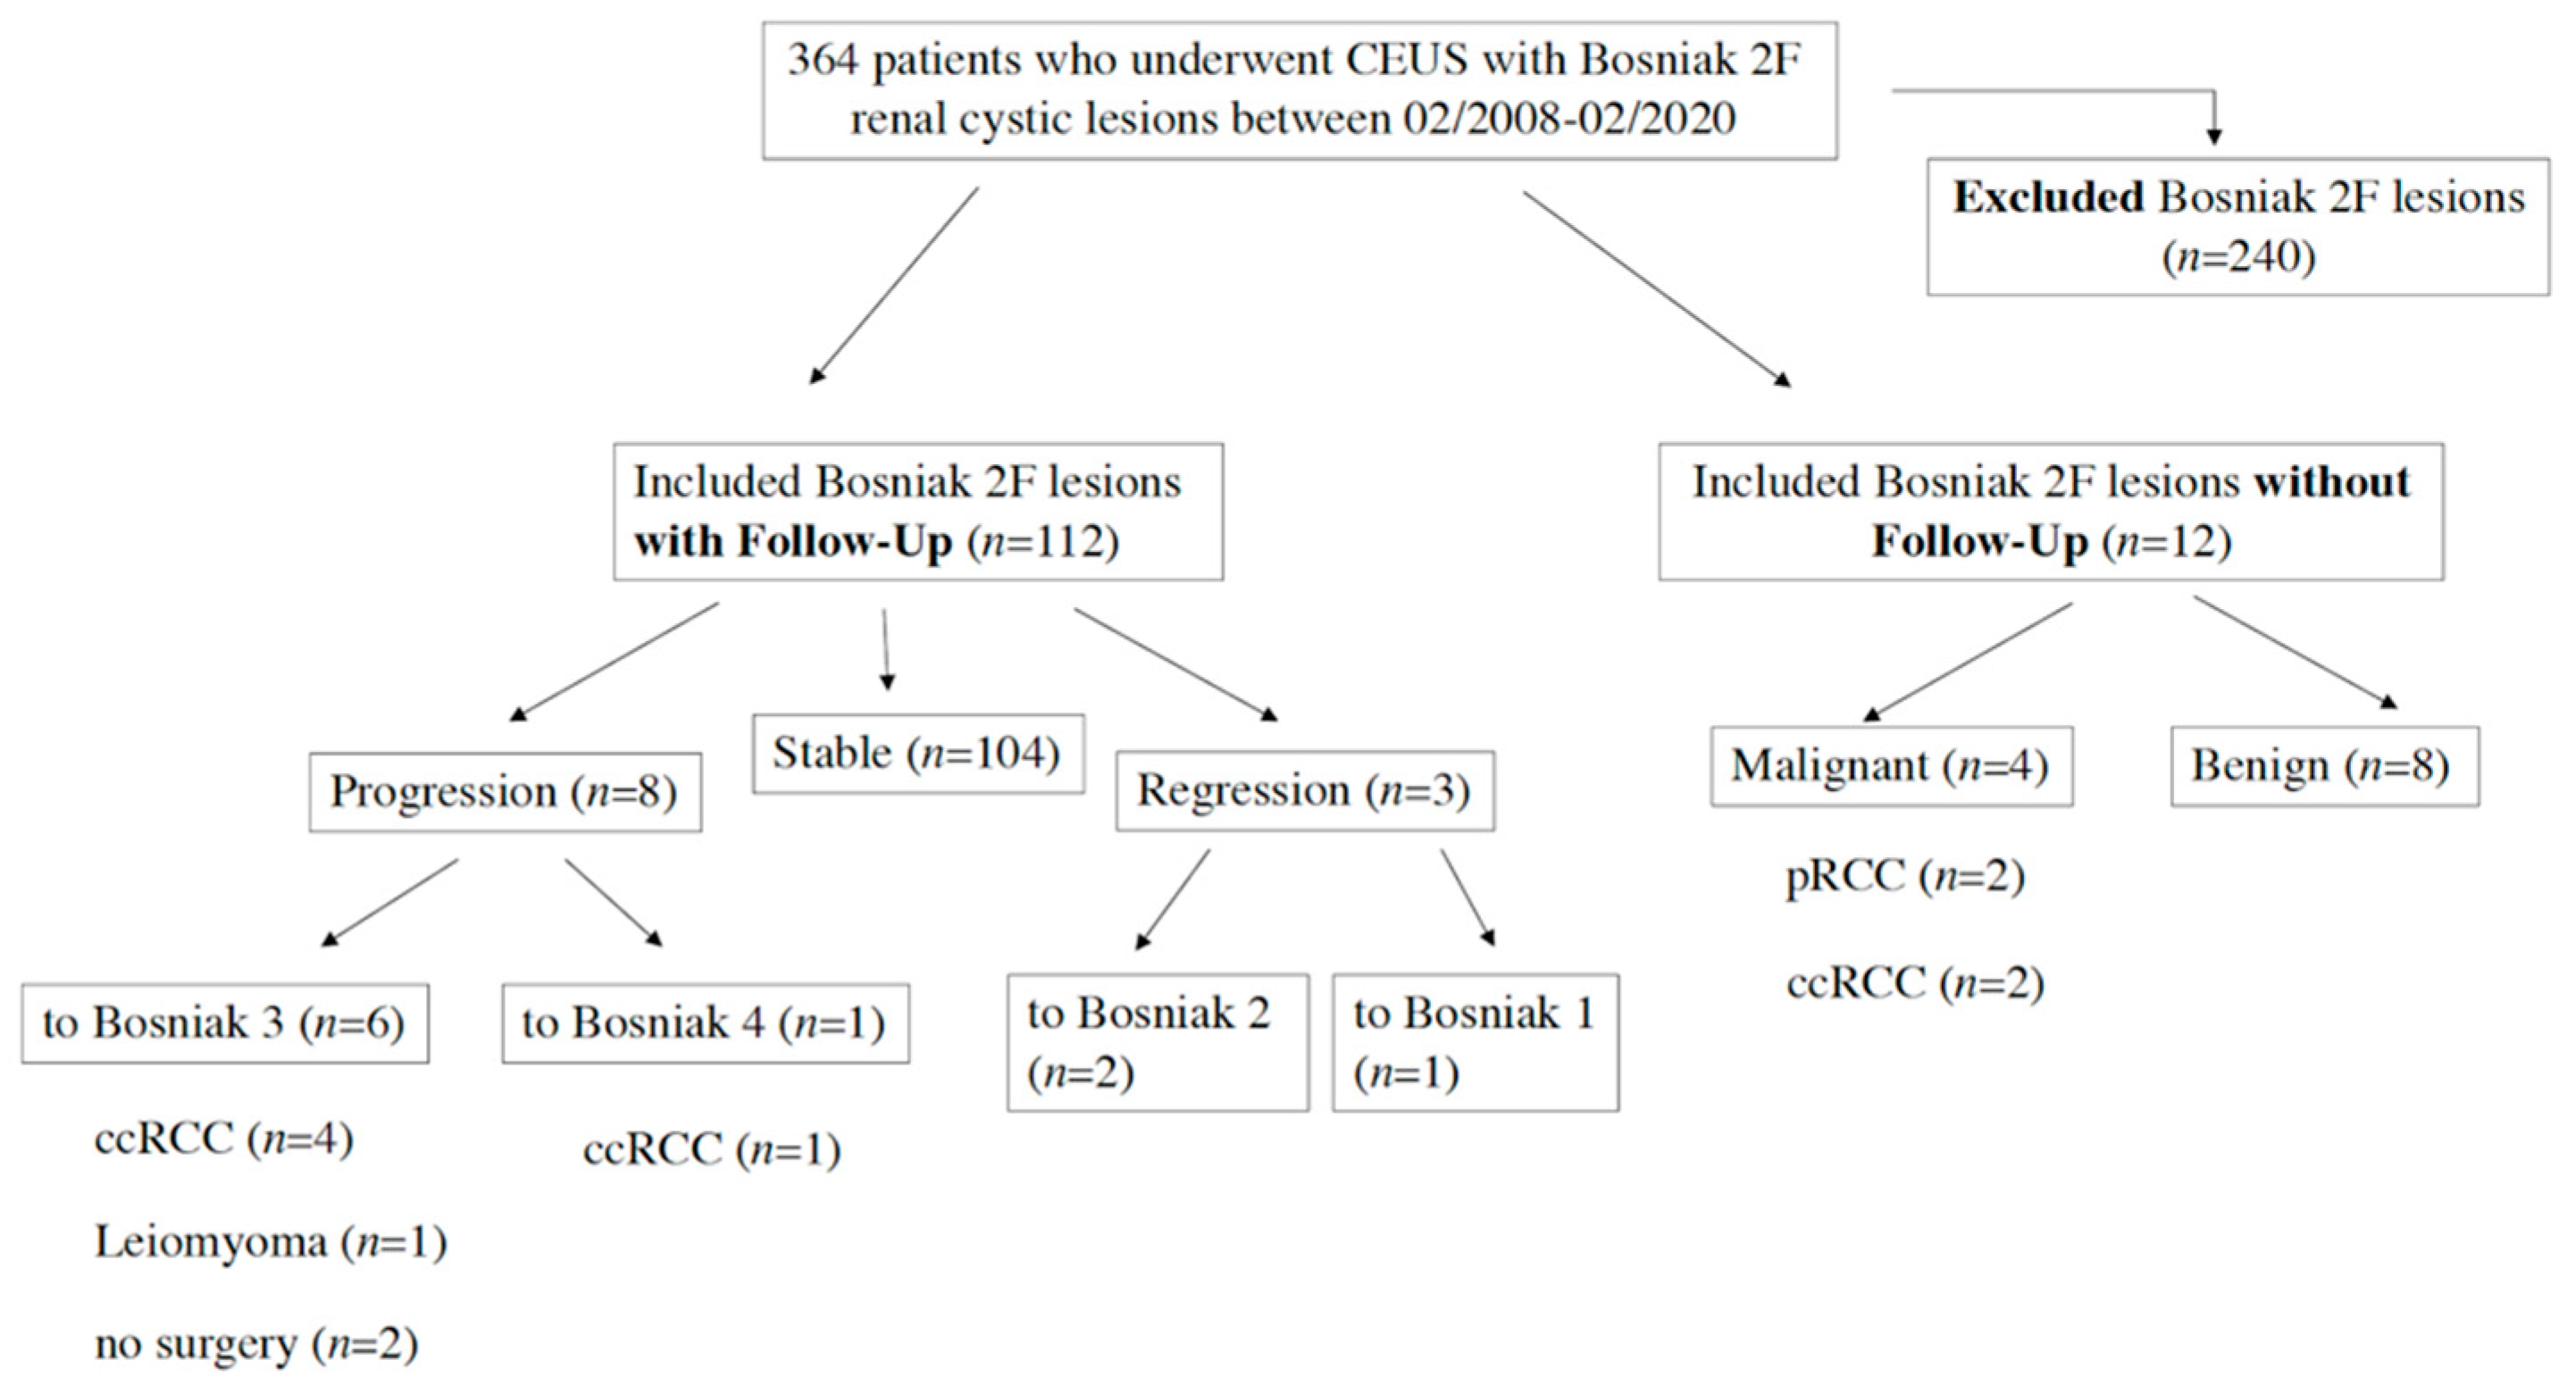

2. Results

4. Materials and Methods

5. Conclusions